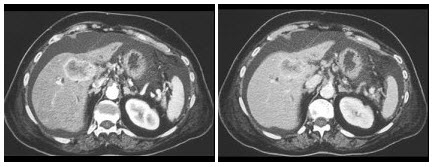

22、多项选择题

男,54岁,左侧腰痛,伴间歇性血尿2个月余,结合所示图像,下列哪项描述正确()

A.左侧肾癌

B.肝内多发转移癌

C.肝癌

D.左肾转移癌

E.腹主动脉旁及左肾门区淋巴结转移